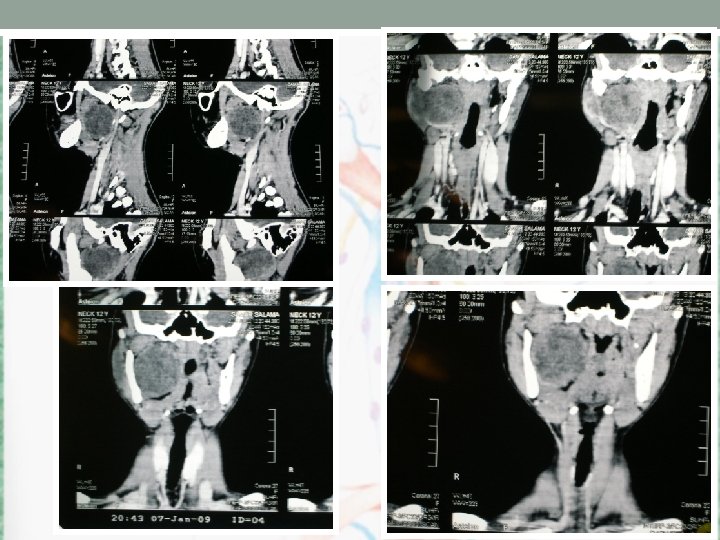

CT scan